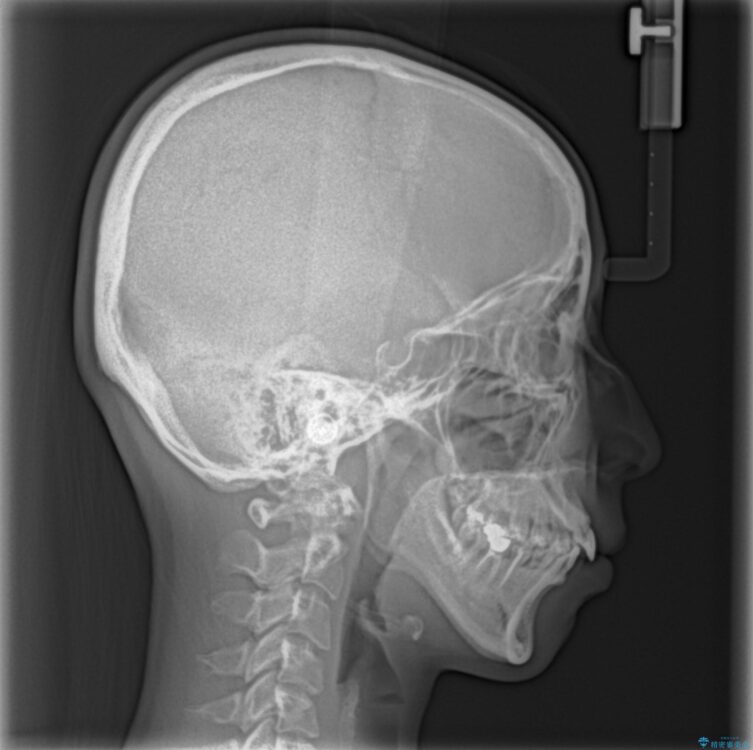

口元の閉じにくさと、奥歯の咬み合わせを気にして来院された患者様です。

左下の大臼歯2本が顕著に舌側に傾斜しているため、まずは奥歯の咬み合わせを改善をし、その後上下左右の第1小臼歯4本を抜歯することで口元を引っ込めながら整えることとしました。

治療前

• 【モニター】出っ歯と咬み合わせを改善 ワイヤー装置の抜歯矯正 治療前画像